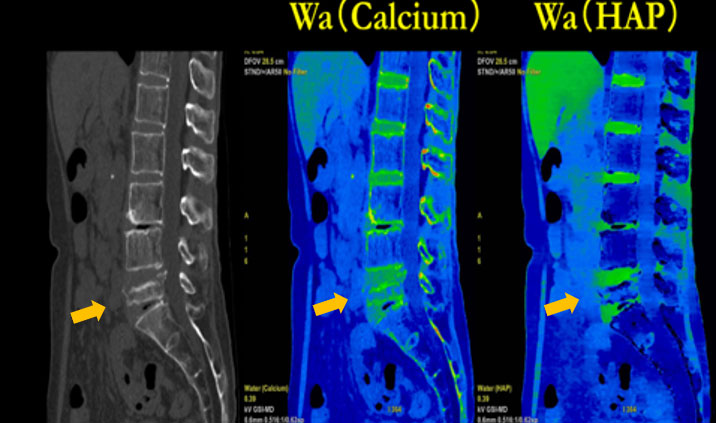

■ Bone Marrow

脊椎圧迫骨折での症例では、骨髄内浮腫の検出を目的に撮影することがあり、水密度画像(Fig5)を作成することで急性期の圧迫骨折の評価を行っている。当院では、MRIが24時間撮影できる環境にあるが、DECTで評価できればMRIの代替検査となり得るため、MRIに比べ簡易的にCTで診断が可能となるため有用である。

RevolutionCT_Minamitohoku06.jpg

Fig5, 早期圧迫骨折の鑑別